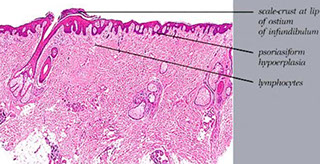

Psoriasiform (epiderm hyplerplasia)

Psoriaform - epidermal hyperplasia

Psoriasis

Papules and plaques w silvery scaling, esp on knees and elbows

- inheritance is complex and polygenetic

- acanthosis w parakeratotic scaling

- inc stratum spinosum and dec stratum granulosum

Micro: Stratum corneum (which has no serum??) has collection of neutros (Munro's abscess)

- loss of granular layer; but no atypia in keratinocytes

- sandwich sign: alternating layers of neutros and parakeratosis

- windy BVs in dermal papillae

- spongiform pustules of Kogoj (???)

Micro: netros crusted at edge of hair follicle, irregular epidermal hyperplasia with mild spongiosis, hyperkeratosis, follicular plugging, and mound of scale crust at the shoulder of the follicle